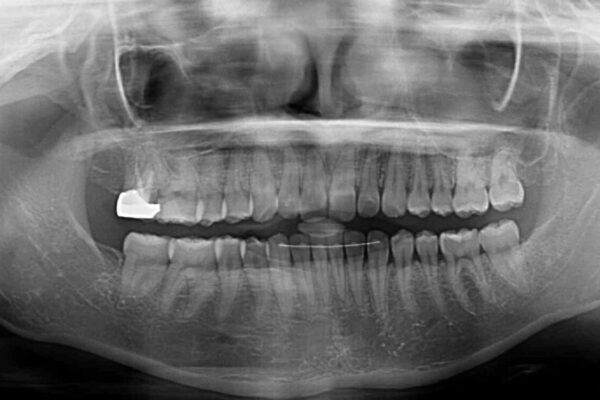

治療前

• 治療途中の奥歯と矯正治療の後戻り インビザライン・ライトによる矯正治療 治療前画像